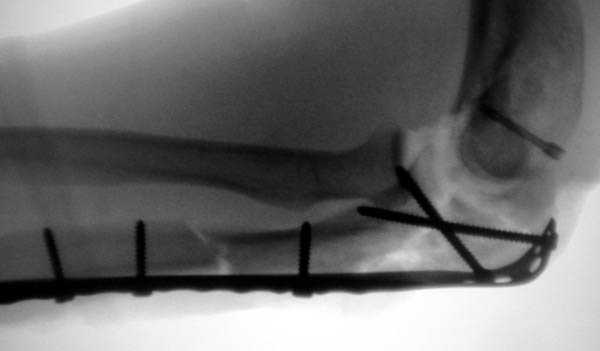

Снимки вот еще какие есть (наши лаборанты пытались сделать что то)

Good day dears colleagues! You presentated only one x-ray proection - lateral- of elbow.Accorden this I thing that this isn't avulsion fracture of olecranon,as usually can to see.This is Monteggia like fracture with subluxation of radial head.If

you can show AP x-ray or more more better CT elbow

I will more sure.Any way more imported of all normal long of ulna.So my recomendation ORIF proximal ulna by LCP - allow normal long by bridging, without attention to continues cortex but attention to articular surfase. On operation examen of radial head,becouse my sence isn't without damage.Operation by standart approach.

Приветствую , Владимир ! У меня был подобный пациент , правда там степень разрушений была поменьше . Обошёлся реконструкционной платой . В Вашем случае основная задача - восстановить суставную поверхность локтевой кости и конгруэнтность сустава ,а также устранить подвывих головки луча (кпереди?)Попробуйте "собрать" на спицах суставную поверхность , затем суставной блок фиксируем к диафизу . Тут , мне кажется , не обойтись без LCP . Пустоты заполнить губчатой костью . Возможно , (повторяю , возможно , хоть и не хочется ) прийдётся виполнить трансартикулярную фиксацию головки луча . Либо , наложить аппарат внешней фиксации для разгрузки сустава и возможных ранних движений.

Снимок, действительно, "не очень". Но глядя на него почему-то возникает очень сильное ощущение, что там и венечный отросток сломан тоже. Что ситуацию здорово усложняет. Причём перелом венечного "III типа" - очень крупный фрагмент, отломанный под самое его основание. А это (без фиксации) уже грозит задней, а возможно - и фронтальной (вальгусной/варусной) нестабильностью.

Это не перелом локтевого отростка! Безусловно сломан венечный отросток и, может оказаться, что и головка луча. Сложный перелом! Доступ задний, фиксация пластиной (LCP) и стягивающими винтами. Только не по Веберу! Положение больного на животе. ЭОП.

При самом большом к Вам уважении, Сергей Анатольевич, не соглашусь. У меня, после того, как добавили "прямой" снимок, сомнений не осталось. Венечный сломан наверняка. Но чтобы судить, насколько это критично для стабильности, нужно иметь строго боковую проекцию. И при этом помнить, что на него крепятся медиальные связки.

Прикрепляю снимок, где обведен фрагмент, несущий на себе венечный отросток (весь он смещён с этим фрагментом или частично - без качественной боковой проекции судить сложно), и отдельно на снимке обведено "ложе", от которого он сместился.

Почему я в данном случае против Вебера (хотя обычно горячий сторонник)? Да потому, что спицам нередко не хватает жёсткости, чтобы удержать предплечье от волярного подвывиха. При таком оскольчатом переломе спицы порой просто "прогибаются" за счёт одного только натяжения проволочной петли и головка луча может уйти в волярный подвывих (может, конечно, и не уйти). Но я бы предпочёл фиксировать всё к жёсткой пластине (включая фрагмент с венечным отростком) и, по возможности, исключить послеоперационную внешнюю иммобилизацию. Накладывать на такой локоть после операции гипс -- означает обрекать его на тяжёлую контрактуру.